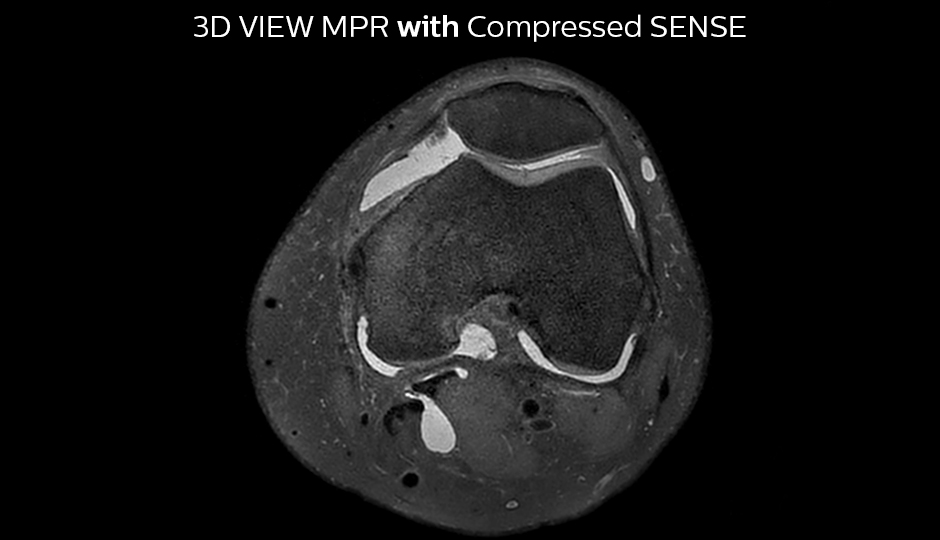

The KSW team also started implementing Compressed SENSE in ankle, elbow, knee and wrist MRI exams, for replacing the 2D PD fat sat with 3D PD fat sat. So far, results look good: it’s possible to obtain a good acquisition time with a high resolution.

A good acquisition time with high resolution is obtained when moving from three 2D acquisitions in three planes to one 3D acquisition with Compressed SENSE. In this example, Compressed SENSE with 3D VIEW PD SPAIR is 50% faster than three separate 2D scans and has improved spatial resolution.

Without Compressed SENSE Scan time 2:55 + 3:37 + 3:51 = 10:23 min. Voxel size 0.55 x 0.65 x 3 mm

Three separate 2D PD scans in three orientations

With Compressed SENSE factor 10 Scan time 5:03 min. Voxel size 0.6 x 0.6 x 0.6 mm

3D VIEW PD SPAIR high resolution knee